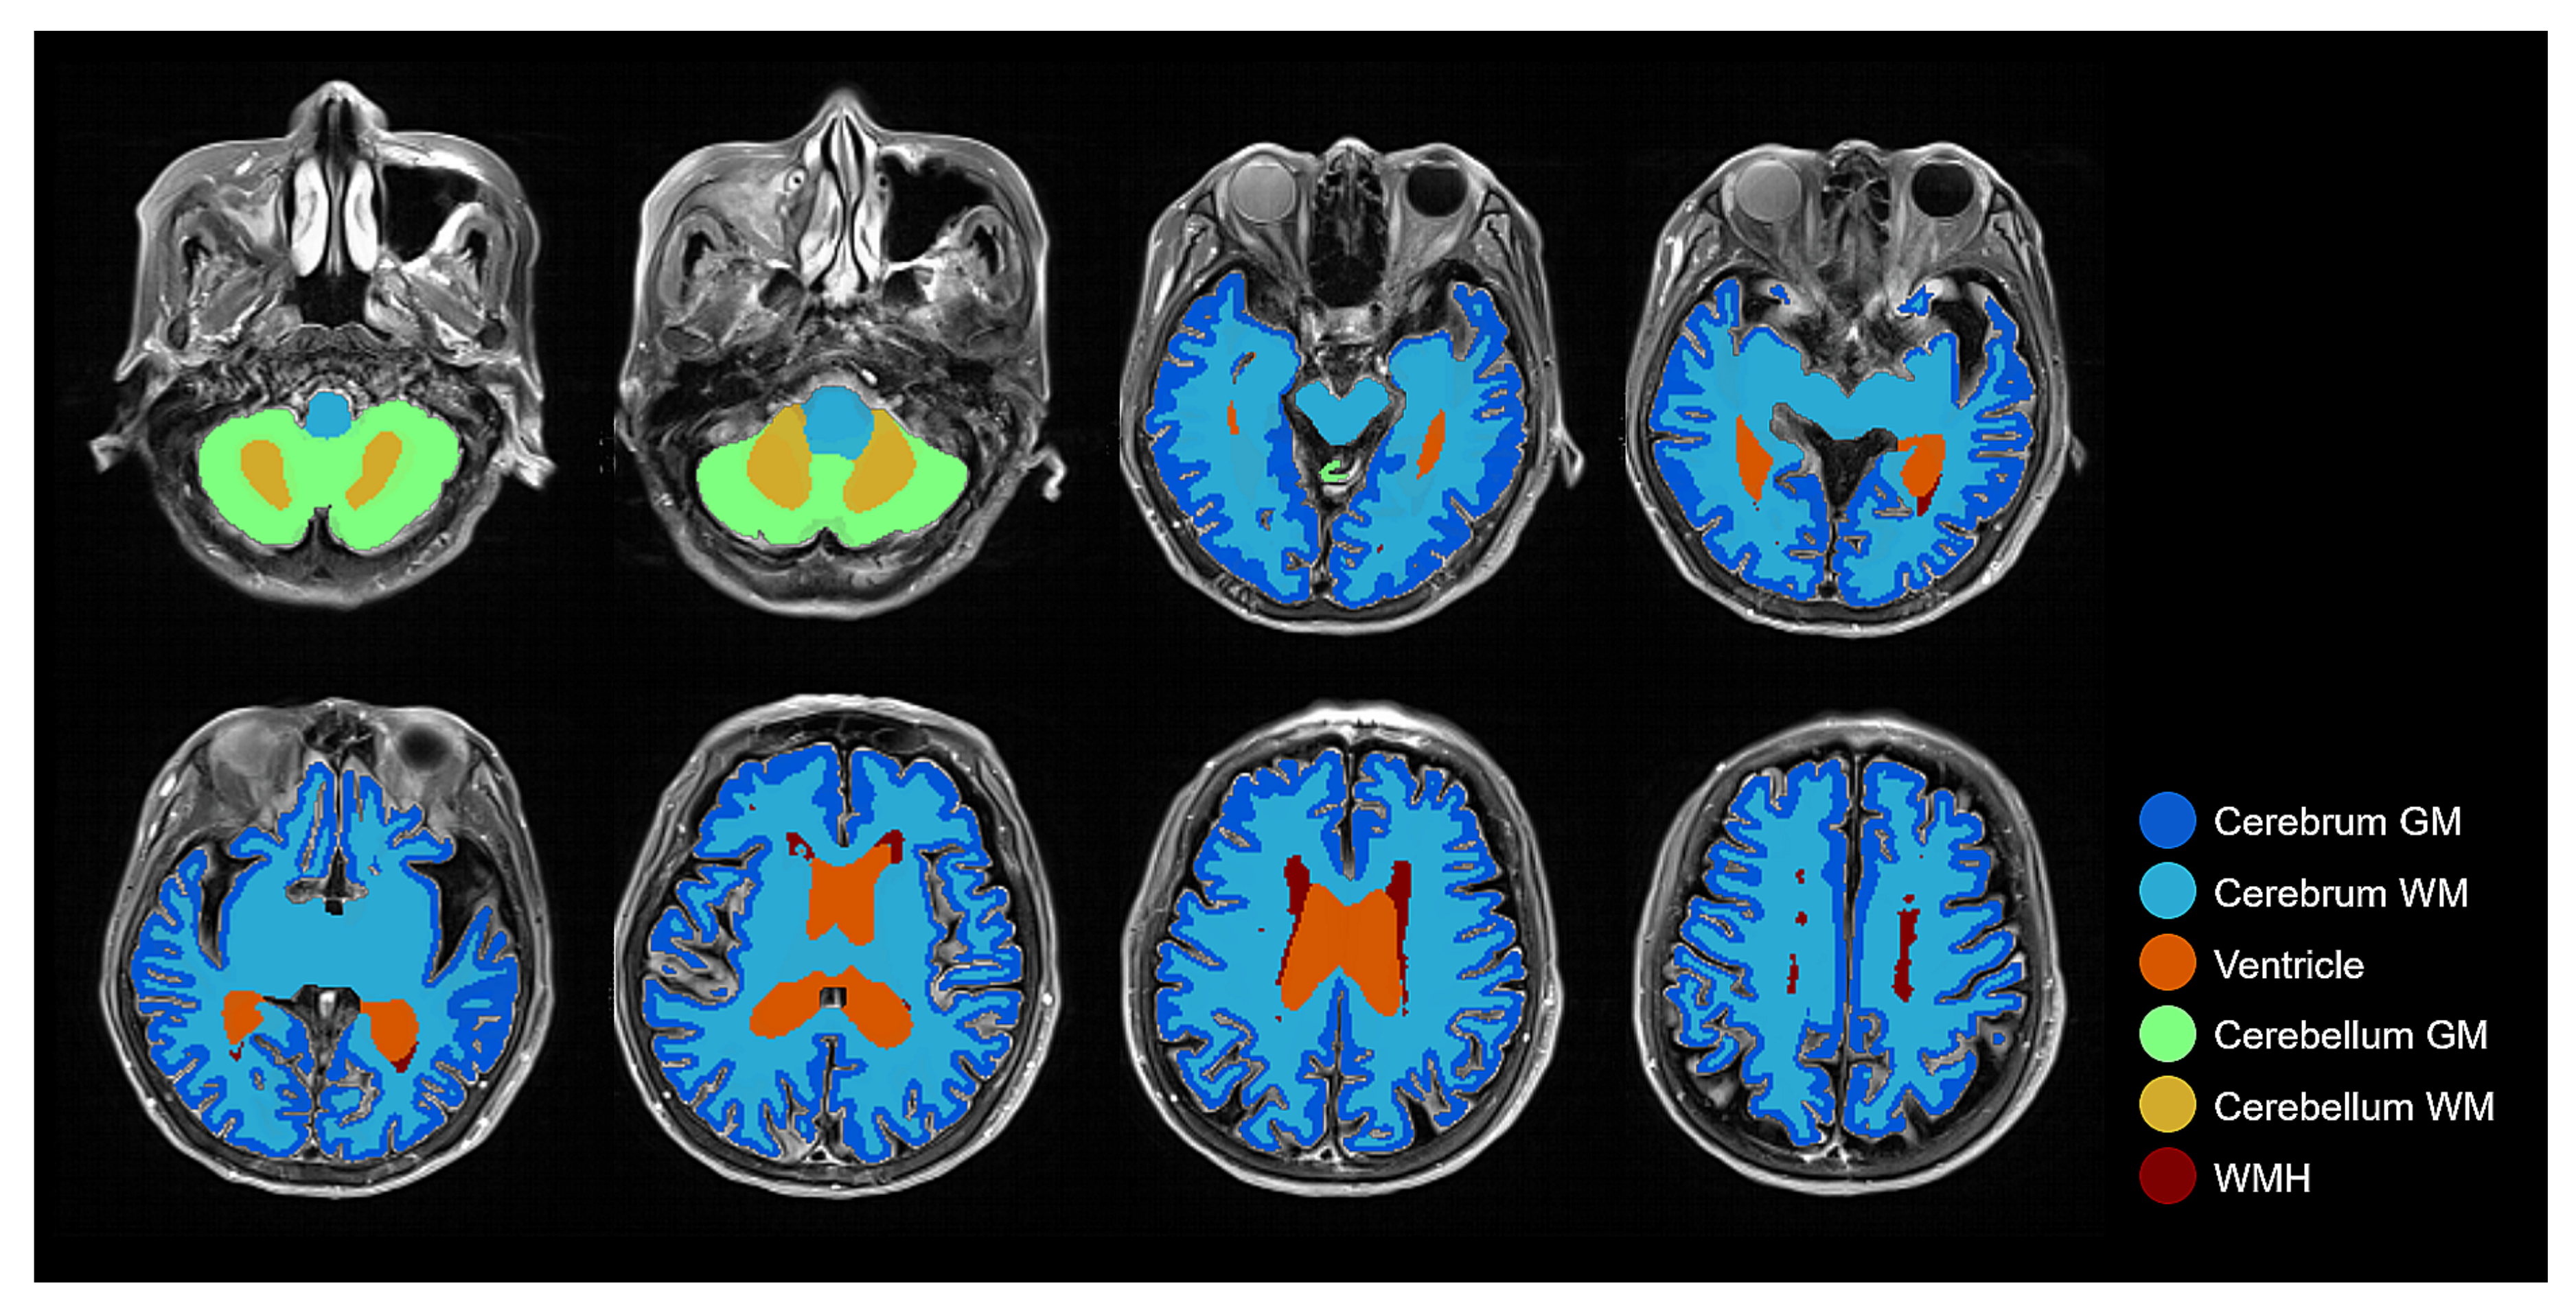

2.3. Brain Tissue Segmentation from FLAIR MRI: Pseudo-Labeling-Based Segmentation

2.4. Brain Tissue Segmentation Enhancement

2.4.1. Deep Learning-Based Initial Segmentation

2.4.2. Morphological Label Correction